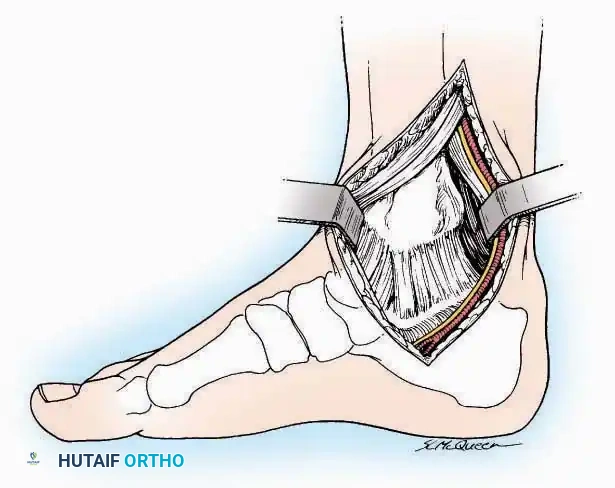

Lateral Approach (Extensile Lateral)

This is the workhorse approach for open reduction and internal fixation (ORIF) of displaced intra-articular calcaneal fractures.

Indications: ORIF of calcaneus fractures, lateral wall exostectomy, subtalar arthrodesis.

Positioning: Lateral decubitus with the operative leg up, or supine with a large bump under the ipsilateral hip to internally rotate the leg.

Surgical Technique:

* Incision: Begin the incision on the lateral margin of the Achilles tendon near its insertion. Extend it distally to a point 4 cm inferior and 2.5 cm anterior to the lateral malleolus. (For trauma, a classic L-shaped extensile incision is often used, dropping straight down anterior to the Achilles, then curving gently toward the base of the 5th metatarsal).

* Superficial Dissection: Divide the superficial and deep fasciae. It is imperative to create a "full-thickness" flap containing skin, subcutaneous fat, and periosteum to prevent flap necrosis.

* Nerve Protection: The sural nerve crosses the proximal and distal limbs of this approach. It must be identified and protected within the anterior flap.

* Deep Dissection: Isolate the peroneal tendons (longus and brevis). Incise and elevate the periosteum below the tendons to expose the lateral wall of the calcaneus.

* Tendon Management: If severe deformity or infection is present, the peroneal tendons may be divided via Z-plasty and repaired at the conclusion of the case, though this is rarely necessary in modern fracture care.